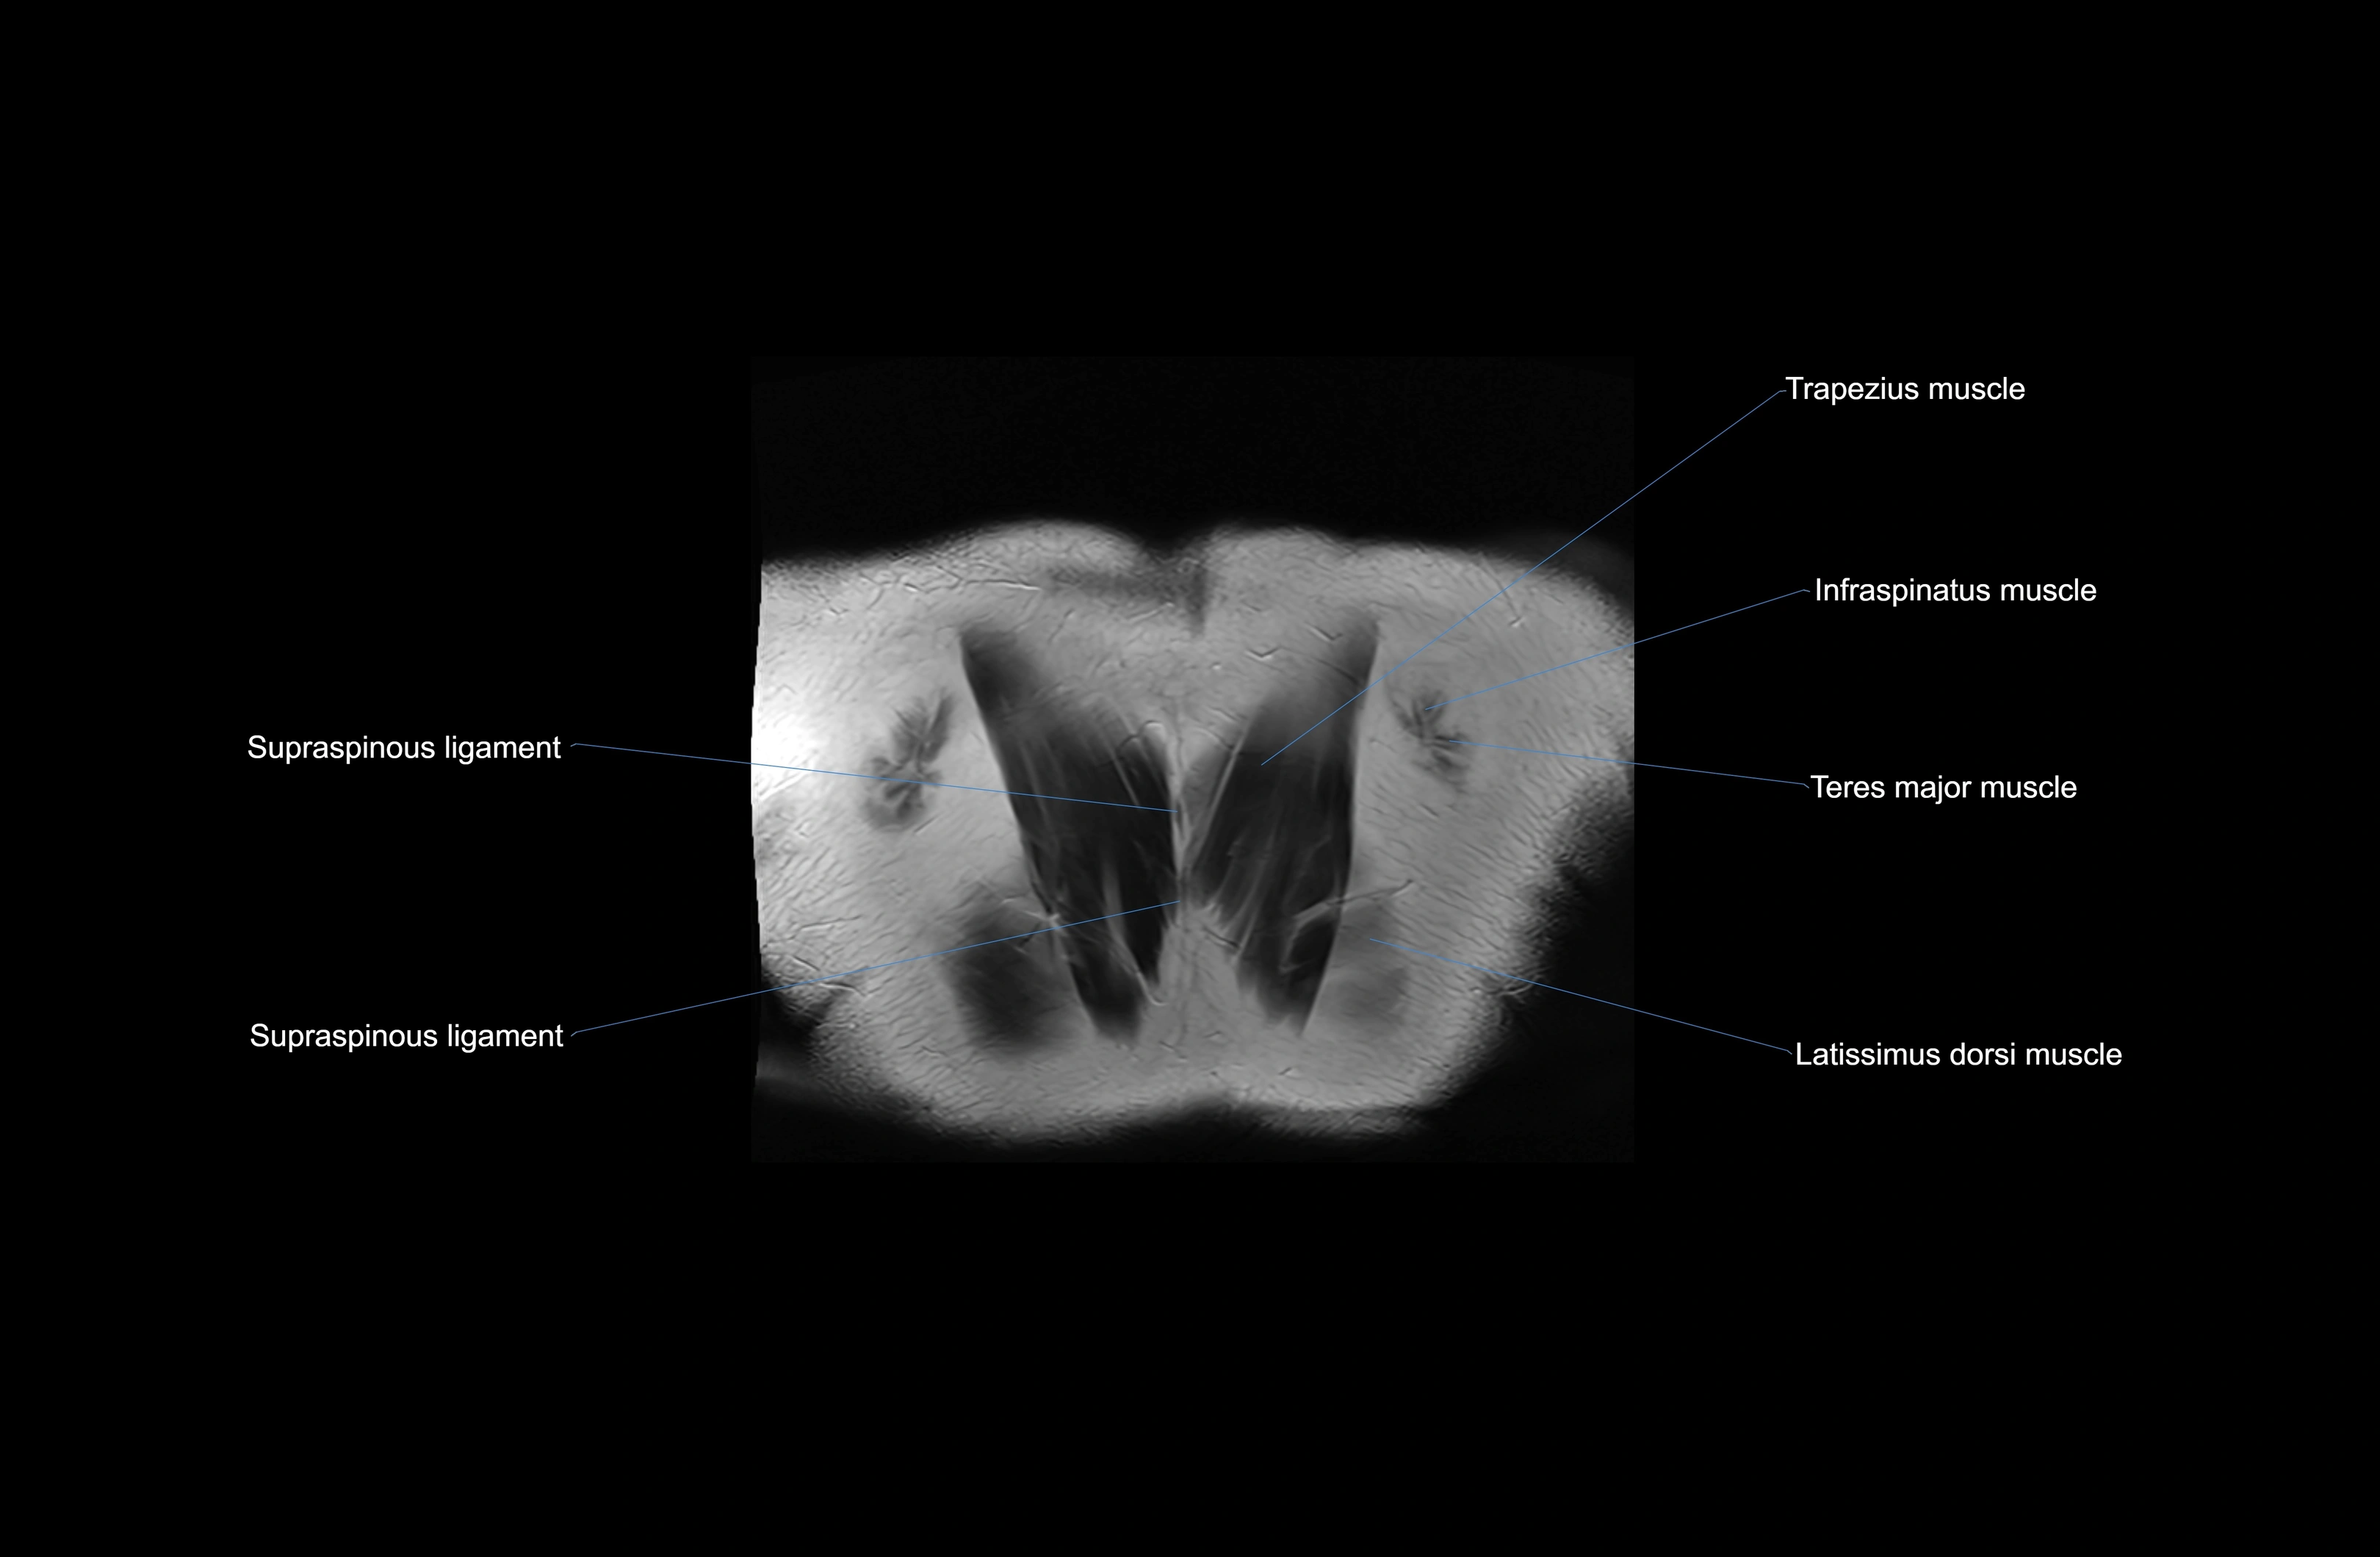

MRI images